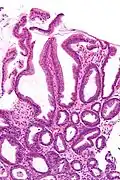

| Micrograph of a reactive gastropathy. H&E stain. | |

- Foveolar hyperplasia (black arrow), as a tortuosity in the "neck" region of the gastric glands.

- Scant or minimal inflammatory cells (white arrow), i.e. lack of large numbers of neutrophils and plasma cells..

- Smooth muscle hyperplasia in the lamina propria (in black oval).

The diagnosis is by examination of tissue, e.g. a stomach biopsy.

High mag. High mag.